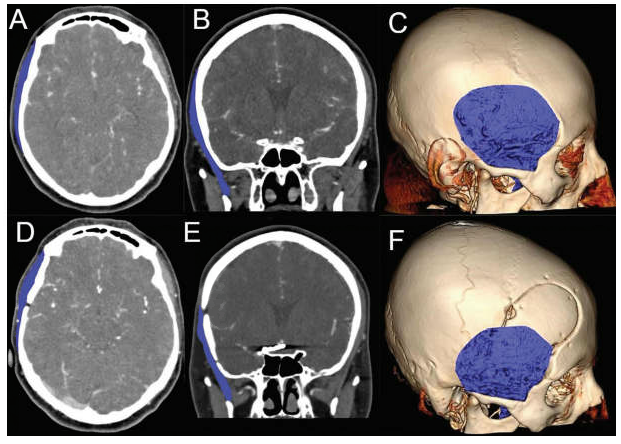

图2:患者因右侧大脑中动脉动脉瘤行改良翼点开颅手术影像资料。(A)术前轴位CT,(B)术前冠状位CT,(C)术前三维图像。(D)术后轴位CT, (E)术后冠状位CT, (F)通过三维CT图像测量右侧颞肌的体积(蓝色显示颞肌)。